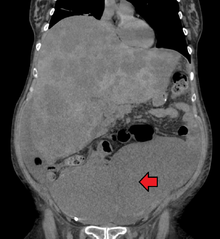

Colon cancer with extensive metastases to the liver

A colorectal cancer is sometimes initially discovered on CT scan.

Presence of metastases is determined by a CT scan of the chest, abdomen and pelvis.[23] Other potential imaging tests such as PET and MRI may be used in certain cases.[23] The latter is often used for rectal lesions to determine its local stage and to facilitate preoperative planning.